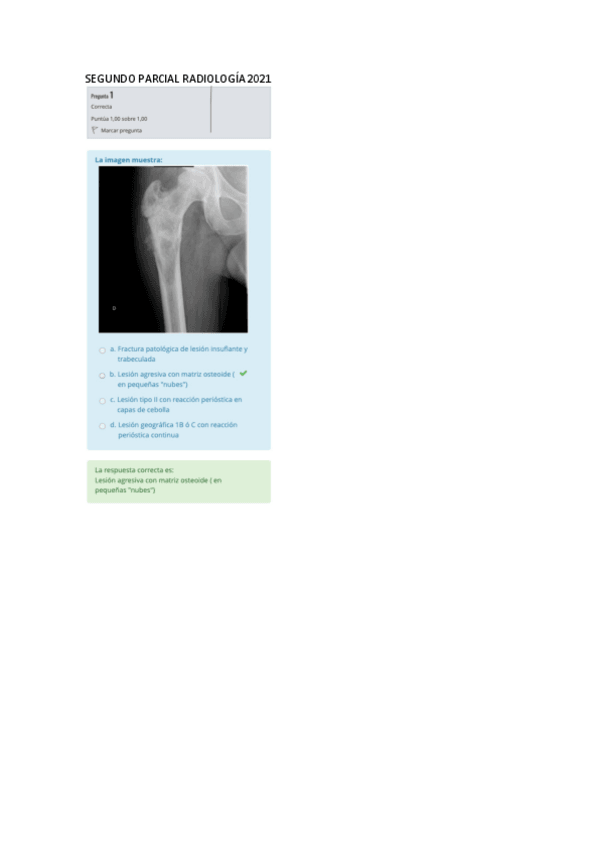

He publicado nuevos apuntes de 2º Radiologia General: SEGUNDO-PARCIAL-RADIOLOGIA-2021.pdf